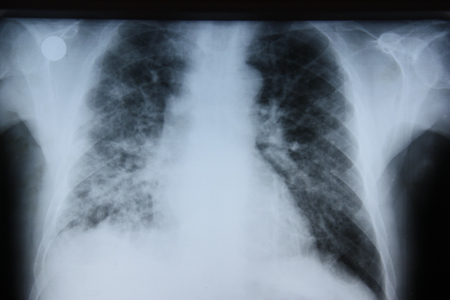

O sarcoma de Kaposi pode causar infiltrado pulmonar persistente.[Figure caption and citation for the preceding image starts]: Radiografia torácica anteroposterior em pneumonia por Pneumocystis jirovecii mostrando infiltrados pulmonares intersticiais bilaterais graves com pneumatocelesDo acervo de Matthew Gingo, UPMC [Citation ends].